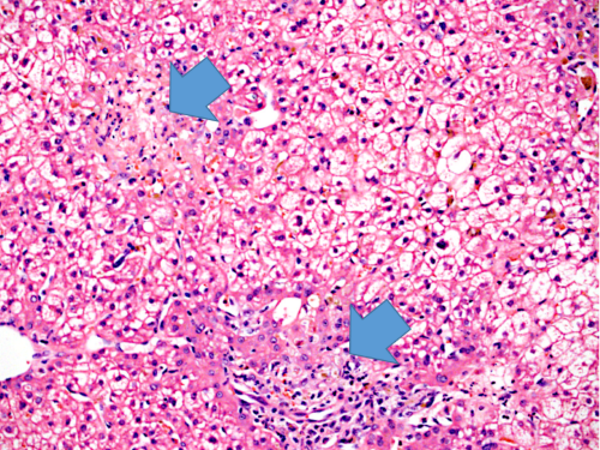

Case 3: Neutrophilic Hepatitis